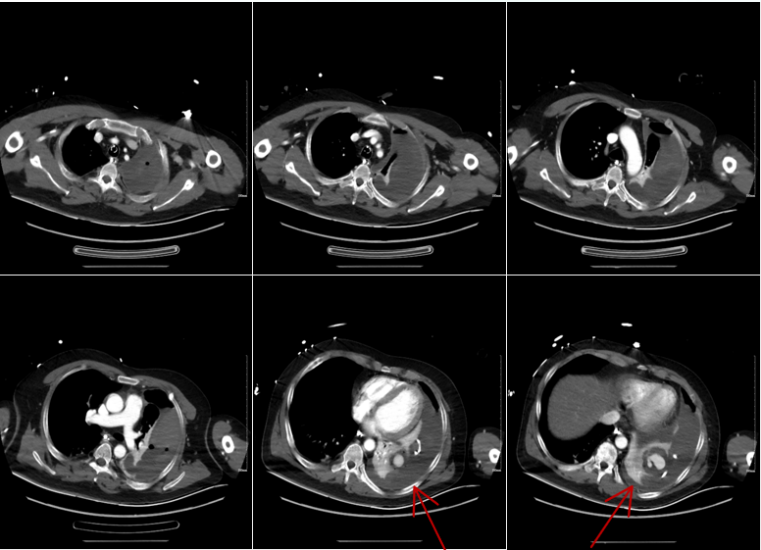

4. 影像学(外院,2025-04-26)

2025年4月26日患者外院胸部CT示:左侧胸腔积液伴左肺膨胀不全,左肺多发蜂窝状密度增高影,提示坏死性病灶可能,左肺上叶实性团块,占位性病变可能,右肺上叶小的厚壁空洞形成(图1)

1  患者外院胸部CT(2025-04-26)